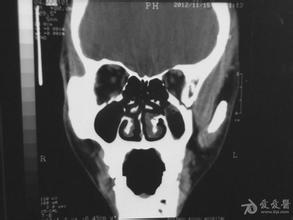

答:瓦氏位(Waters氏位是检查鼻窦最常用的投照位置。瓦氏位可观察额窦、筛窦及上颌窦。

答:瓦氏位(Waters氏位)、柯氏位(Cald well氏位)是检查鼻窦最常用的投照位置。瓦氏位可观察额窦、筛窦及上颌窦,柯氏位则可更好地观察额窦及筛窦。

瓦氏位:片子显示,双侧上颌窦透光度减低,窦腔浑浊,其

答:可清晰显示所有副鼻窦,可判断副鼻窦炎的严重程度和鉴别炎症和肿瘤。 建议先详细检查清楚,再用药和住院治疗,不可盲目住院。建议CT副鼻窦冠状位扫描,确诊后再讨论治疗问